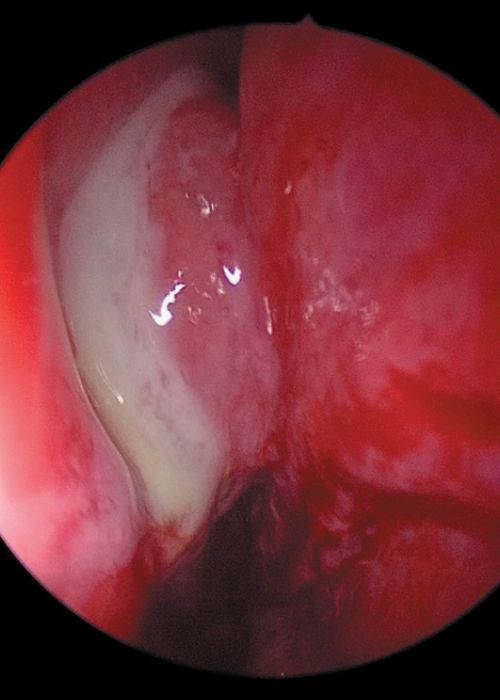

Sialoendoscopia en las patologías obstructivas de las glándulas salivales